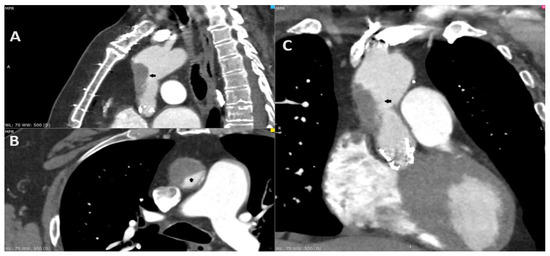

Figure 2. After the consultation with the cardiac radiologist, the third ECG-gated cardiac CT was performed on the eighth day after the initial CT to access both the aorta and coronary arteries. To increase the quality of the image, an additional beta-blocker and nitroglycerin were administered before examination. The CT revealed aortic valve prosthesis thrombosis (A; red arrow) and a reduction in aortic thrombosis (B; orange arrow). The previous thrombus site was localized to originate within the ascending aorta graft, which was covered by soft tissue that resembled an ulcer. The probable dissection of the neointima along the prosthesis was the suspected cause of the initial aortic thrombosis (C,D; black arrow).